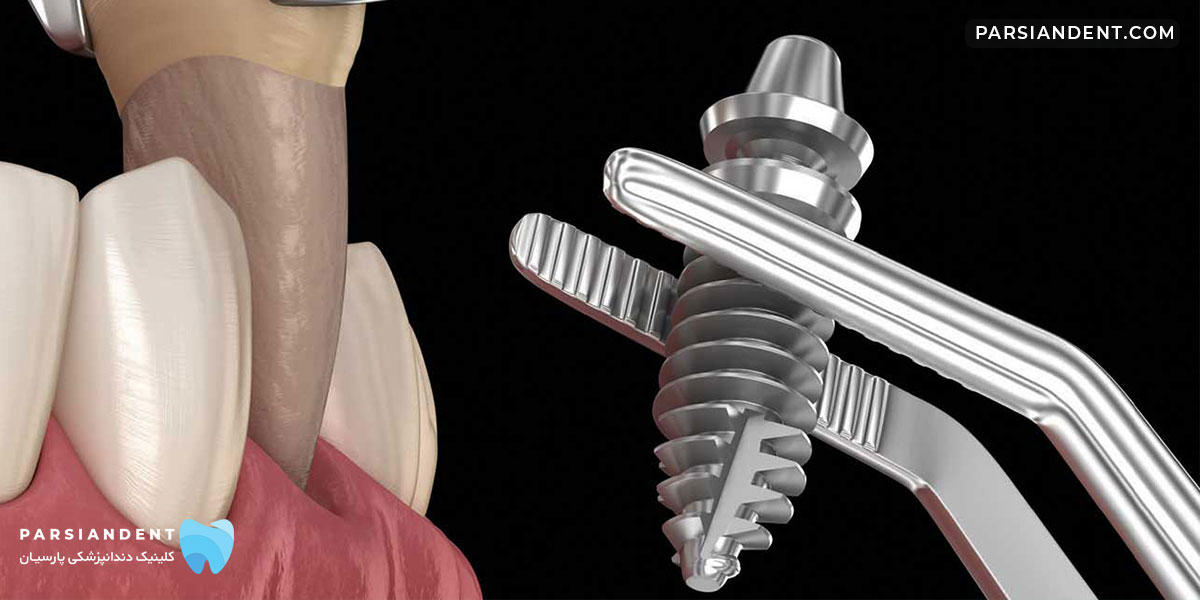

ایمپلنت دندان Dental implant عموما یک فلز از جنس تیتانیوم بوده که در داخل استخوان فک قرار گرفته و بر روی آن ساختارهای پروتزی مانند روکش قرار میگیرد. هنگامی که یک دندان به دلایل مختلف قابل نگهداری نبوده و کشیده میشود یا حتی وقتی که یک فرد به طور مادر زادی یک دندان را ندارد، میشود به جای دندان از دست رفته، ایمپلنت قرار داد.

در کاشت ایمپلنت، فرایند انجام چند مرحله ای است، بدین صورت که ابتدا باید با جراحی به استخوان فک بیمار دسترسی پیدا نمود. سپس با جایگذاری پایه ایمپلنت که به فیکسچر موسوم است، شرایط برای جوش خوردن پایه با استخوان فک فراهم می گردد، با گذر زمان این اتصال برقرار می گردد. زمان لازم برای جوش خوردن ایمپلنت گاهی چندین ماه است. در مرحله بعدی روکش ساخته شده برای ایمپلنت نصب می گردد.

- جراحی ایمپلنت: در این مرحله، ایمپلنتهای دندان در استخوان فک جایگذاری میشوند. اگرچه این مرحله به نسبت سریع انجام میشود، اما نیاز به جراحی کوچکی دارد. در برخی موارد، استفاده از تکنولوژیهای پیشرفته مانند راهنمایی سهبعدی میتواند دقت و موفقیت این مرحله را افزایش دهد.